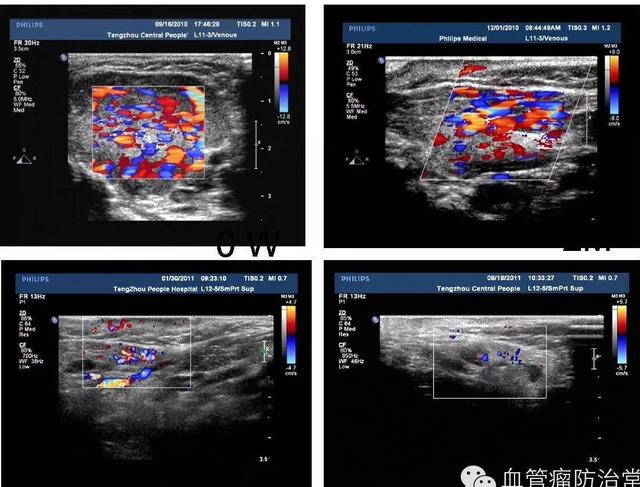

超聲引導(dǎo)下聚桂醇硬化治療血管瘤后血流信號明顯減少